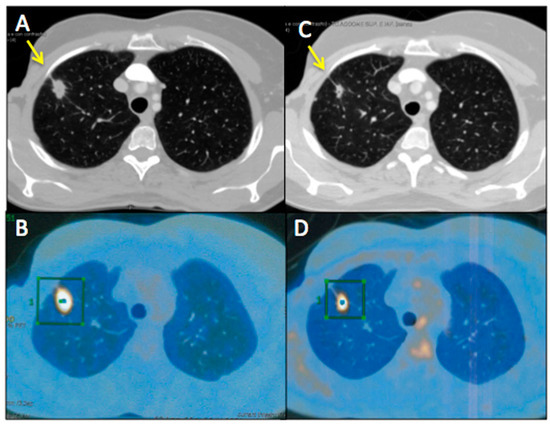

Figure 2 represents an exemplar case of a patient judged as SD at the timepoint-1 evaluation.

Figure 3. A 55-year-old female affected by breast cancer with lung metastasis, subjected to 12 cycles of Bevacizumab-based chemotherapy and 24 hyperthermia sessions on the thorax, as first-line. Baseline Multidetector Contrast Enhancement Computed Tomography (MDCT) (A) showed metastasis in the superior right lobe of the lung (diameter: 17 mm × 12 mm, yellow arrow), confirmed by the increased 18F-Fluorodeossiglucose (18F-FDG) uptake on Positron Emission Tomography/CT (PET/CT) images in the same sites (green square, B). Timepoint-2 MDCT (C) evaluation demonstrated size decrease of lung metastasis (diameter 14 mm × 7 mm, yellow arrow) with 18F-FDG uptake decrease on PET/CT images (green square, D). According to mRECIST, patient was classified as PR. Ca15.3 and CEA values evaluated at baseline were 830 UI/mL and 135 ng/mL, respectively; while Ca15.3 and CEA values evaluated at timepoint-2 were 115 UI/mL and 40 ng/mL, respectively. Side effects reported were limited to asthenia and peripheral sensory neuropathy.